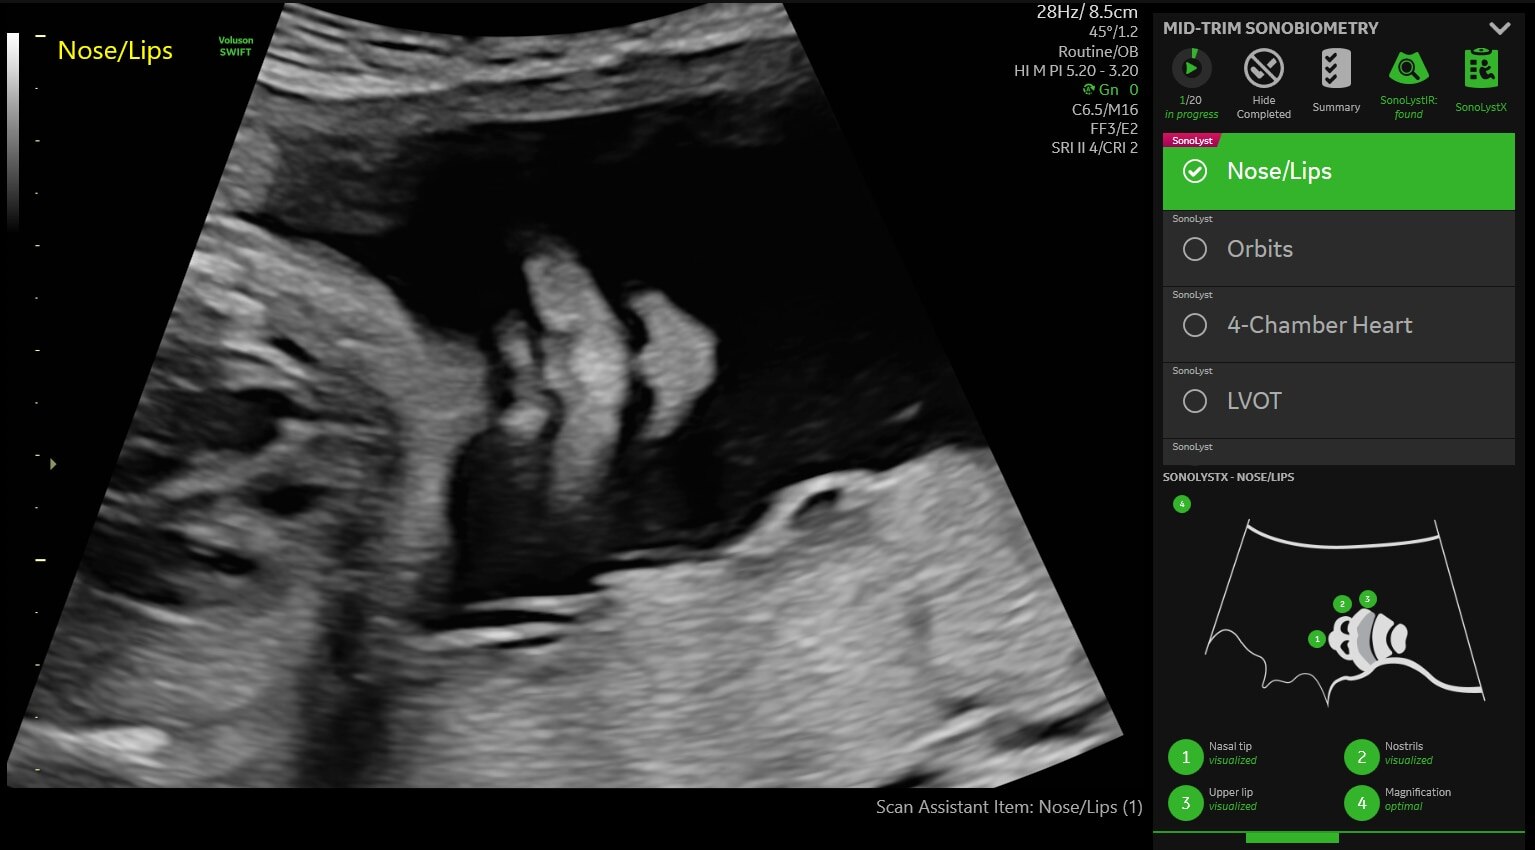

• SonoLystX: Build and refine your skills with SonoLystX. Using AI, the system compares the image or view acquired to standard criteria accepted by experts to ensure it meets clinical standards.